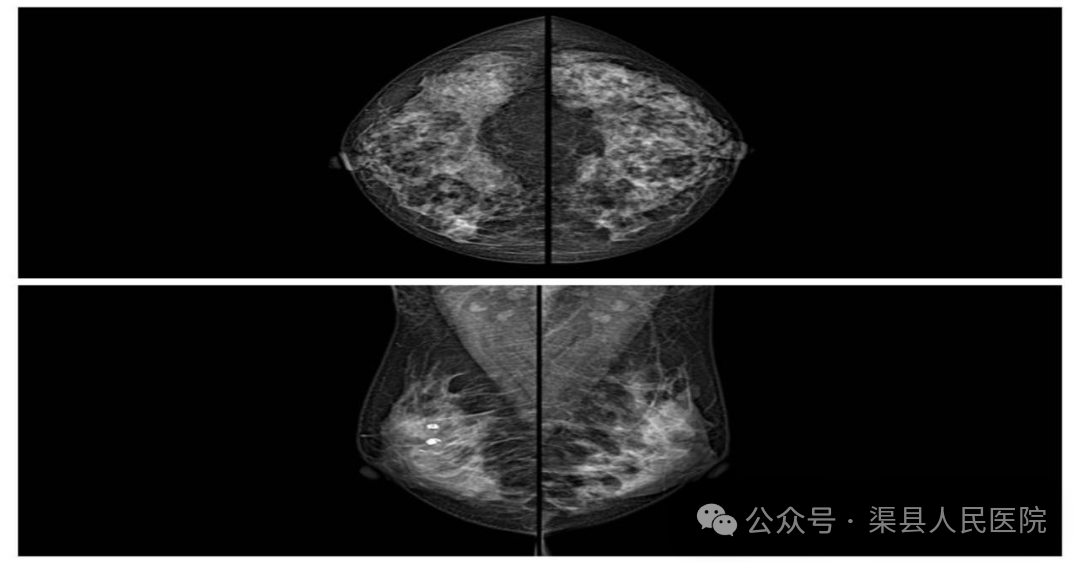

一方面,对于40岁以上的女性来说,随着年龄的增长,乳腺组织逐渐退化,脂肪组织比例相对增加,乳腺钼靶检查的效果会更好。在这个年龄段,乳腺癌的发病风险也逐渐升高。每三年进行一次钼靶检查能够提高早期乳腺癌的发现率,有助于在癌症处于较早期、更易治疗的阶段发现病变。例如,在钼靶图像上可以清晰地看到一些早期乳腺癌呈现出的微小钙化簇或者结构扭曲等异常表现。

钼靶影像

另一方面,乳腺钼靶检查是利用X射线来成像,虽然它对发现微小钙化灶(这可能是早期乳腺癌的重要征象)等病变非常有效,虽有辐射,辐射量小于CT检查。三年一次是比较合理的频率,可以在有效筛查疾病和减少辐射危害之间取得平衡。